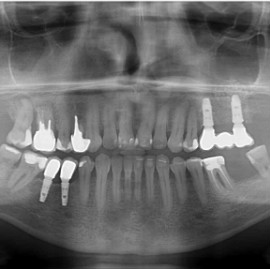

Lat 50, pół roku przed rozpoczęciem leczenia implantologicznego przestał palić papierosy. Znacząca poprawa higieny, pacjent silnie zmotywowany. Po regeneracji kości i rekonstrukcji tkanek miękkich odbudowa sześciu zębów na koronach porcelanowych. Na zdjęciu widoczna ilość i jakość tkanki kostnej po rekonstrukcji. W porównaniu ze stanem początkowym uzyskano znaczącą poprawę warunków kostnych nie do osiągnięcia metodami sterowanej regeneracji kości z użyciem reklamowanych markowych błon kolagenowych i dosypaniem kości z butelki.